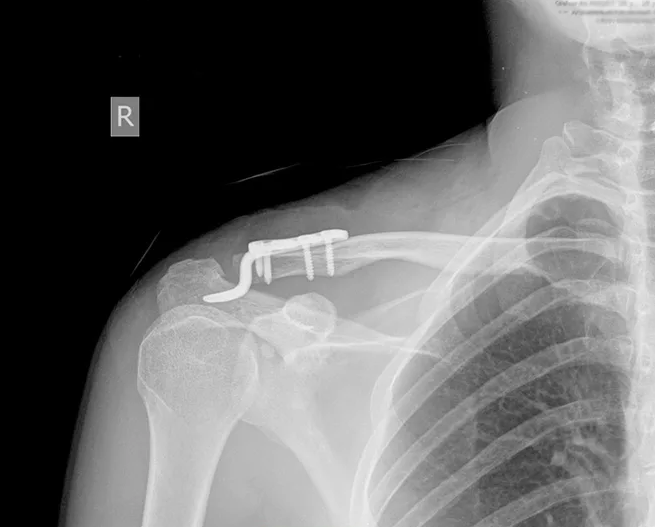

Больному после клинико-лабораторных и инструментальных: (рентгенологических и МСКТ) исследований выполнен накостный остеосинтез устройством при вывихе акромиального конца ключицы под регионарным наркозом (рис. 3).

В послеоперационном периоде пациенту назначены препараты для поддержки консолидации, проводилась антикоагулянтная терапия. Спустя 8 недель после операции проведена контрольная рентгенография и, в связи с отсутствием вторичного смешения отломков и начальными признаками консолидации перелома, разрешена дозированная нагрузка на конечность. Период реабилитации протекал без осложнений. Получены удовлетворительные анатомо-функциональные результаты, восстановление функции конечности (рис. 4).